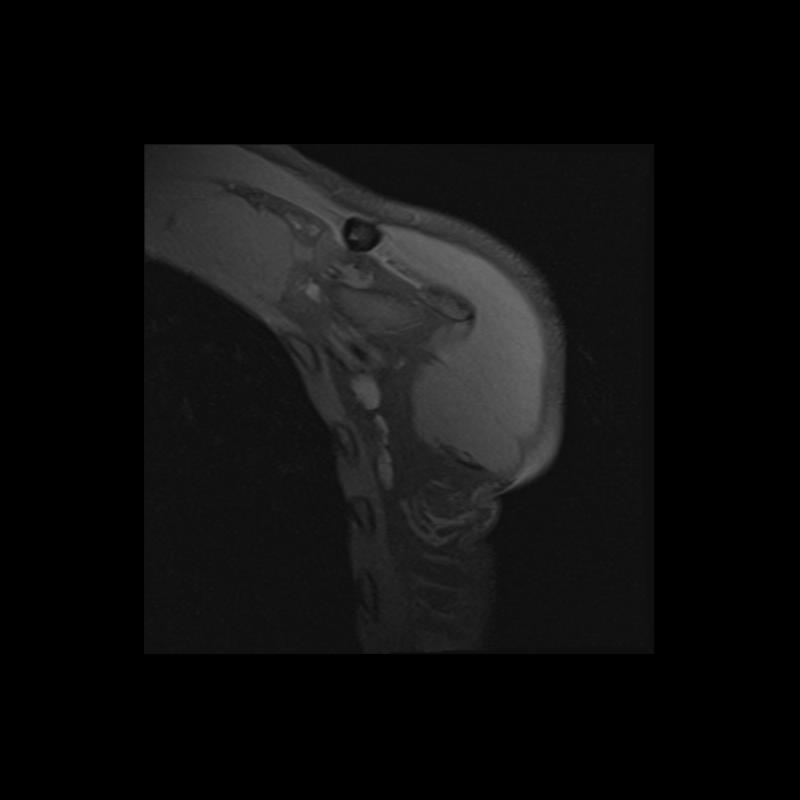

Shoulder MRI Anatomy